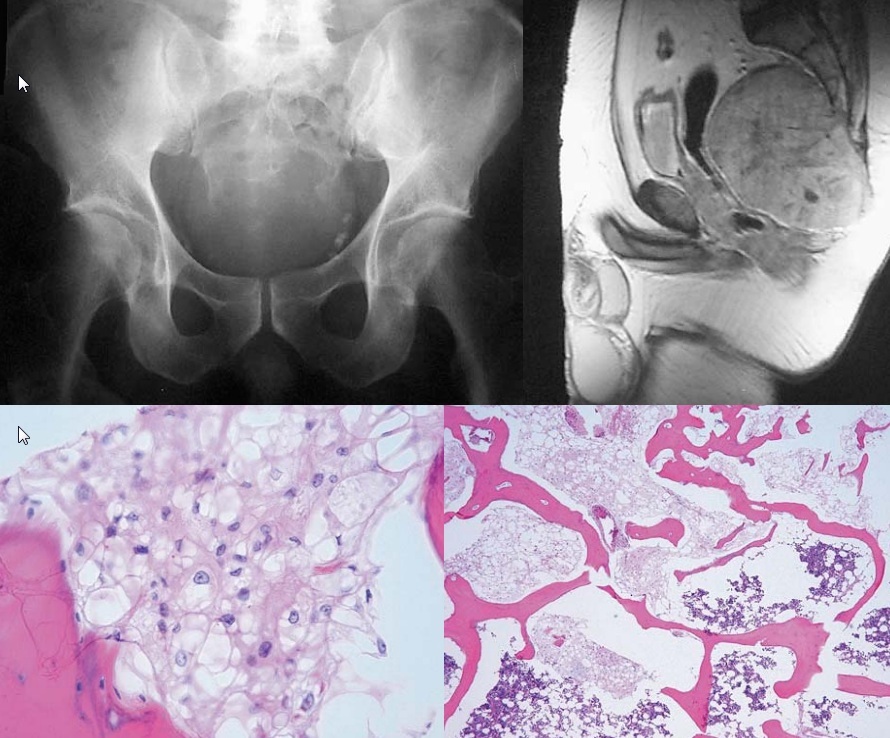

60 yo, CD20 positive

Staging and treatment

bone marrow aspiration and biopsy are required for staging

cyclophosphamide, doxorubicin, prednisone and vincristine